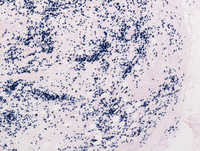

Figure 5: Breast lump-Kappa and Lambda stains

Both the stains were positive depicting the polyclonal nature of infiltrating plasma cells (Left image- Kappa; Right image - Lambda).